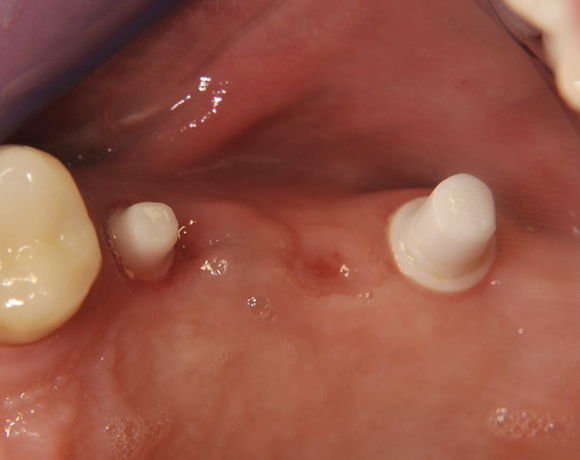

Im vorliegenden Patientenfall wurden für die Zähne 25 und 27 jeweils ein Implantat gesetzt. Nachdem die Implantate eingeheilt waren, wurde 25 – 27 mit einer Brücke versorgt.

Der prothetische Teil